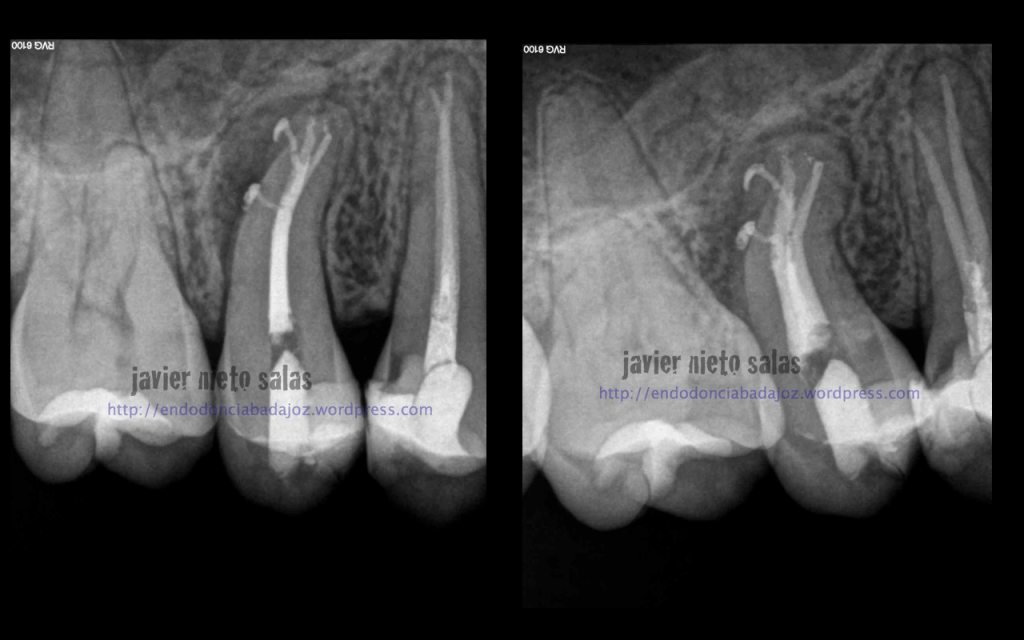

Después de unos 9 meses, la paciente nos llegó a revisión, la lesión ha regenerado correctamente, éxito en el tratamiento:

Este segundo caso, después de estudiar la Rx, vemos un defecto en la furca, y ¿porqué no puede ser el origen las endotoxinas y demás productos de las bacterias intraconducto que colonizan un conducto lateral en ese nivel medio? ( 15% según Vertucci)

Volvemos a ver a la paciente a los 9 meses y vemos como la lesión ha regenerado correctamente y la lesión en furca va desaparecido.